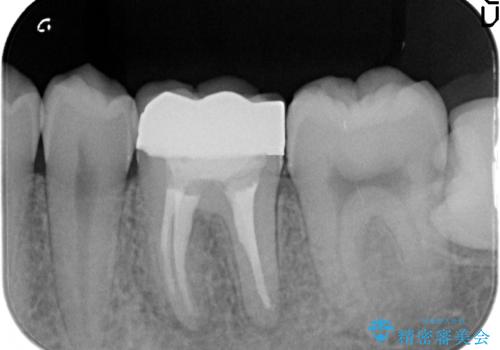

- 他院にて治療途中の歯を診て欲しいといらっしゃった方の症例です。

X線上で根尖病変を認めたため再根管治療を行い、オールセラミッククラウンによる補綴を行いました。